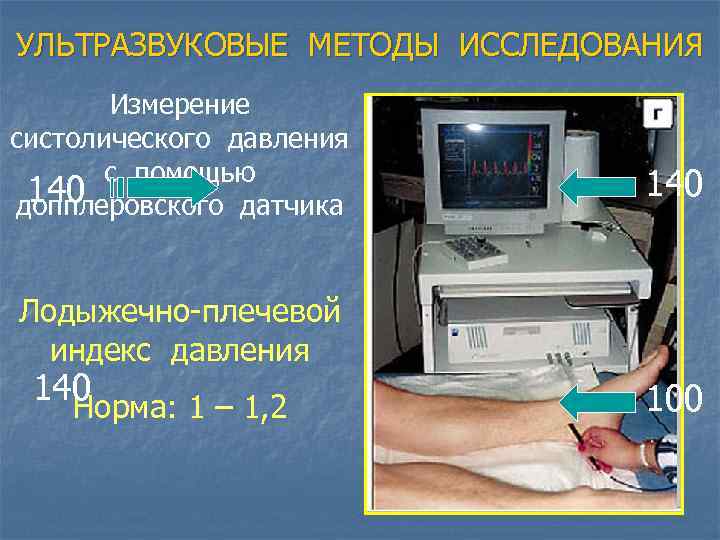

УЛЬТРАЗВУКОВЫЕ МЕТОДЫ ИССЛЕДОВАНИЯ Измерение систолического давления с помощью 140 допплеровского датчика 140 Лодыжечно-плечевой индекс давления 140 Норма: 1 – 1, 2 100